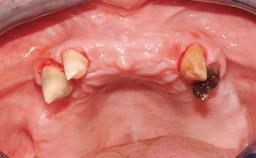

Rehabilitating an Edentulous Maxilla with a Fixed Dental Prosthesis Following Provisional Immediate Loading

This case features the flapless computer-guided placement of 7 bone-level implants, distributed to provide maximal support for the prosthetic framework. A rigid one-piece metallic framework was utilized as an interim restoration to reduce the risk of fracture associated with this prosthetic design. As part of the clinical examination, the SAC Assessment Tool was used, resulting in a surgical and restorative risk classification as “complex”.

Case Type Edentulous Maxilla

Defining Characteristics Fully edentulous upper jaw to be rehabilitated with four or more implants